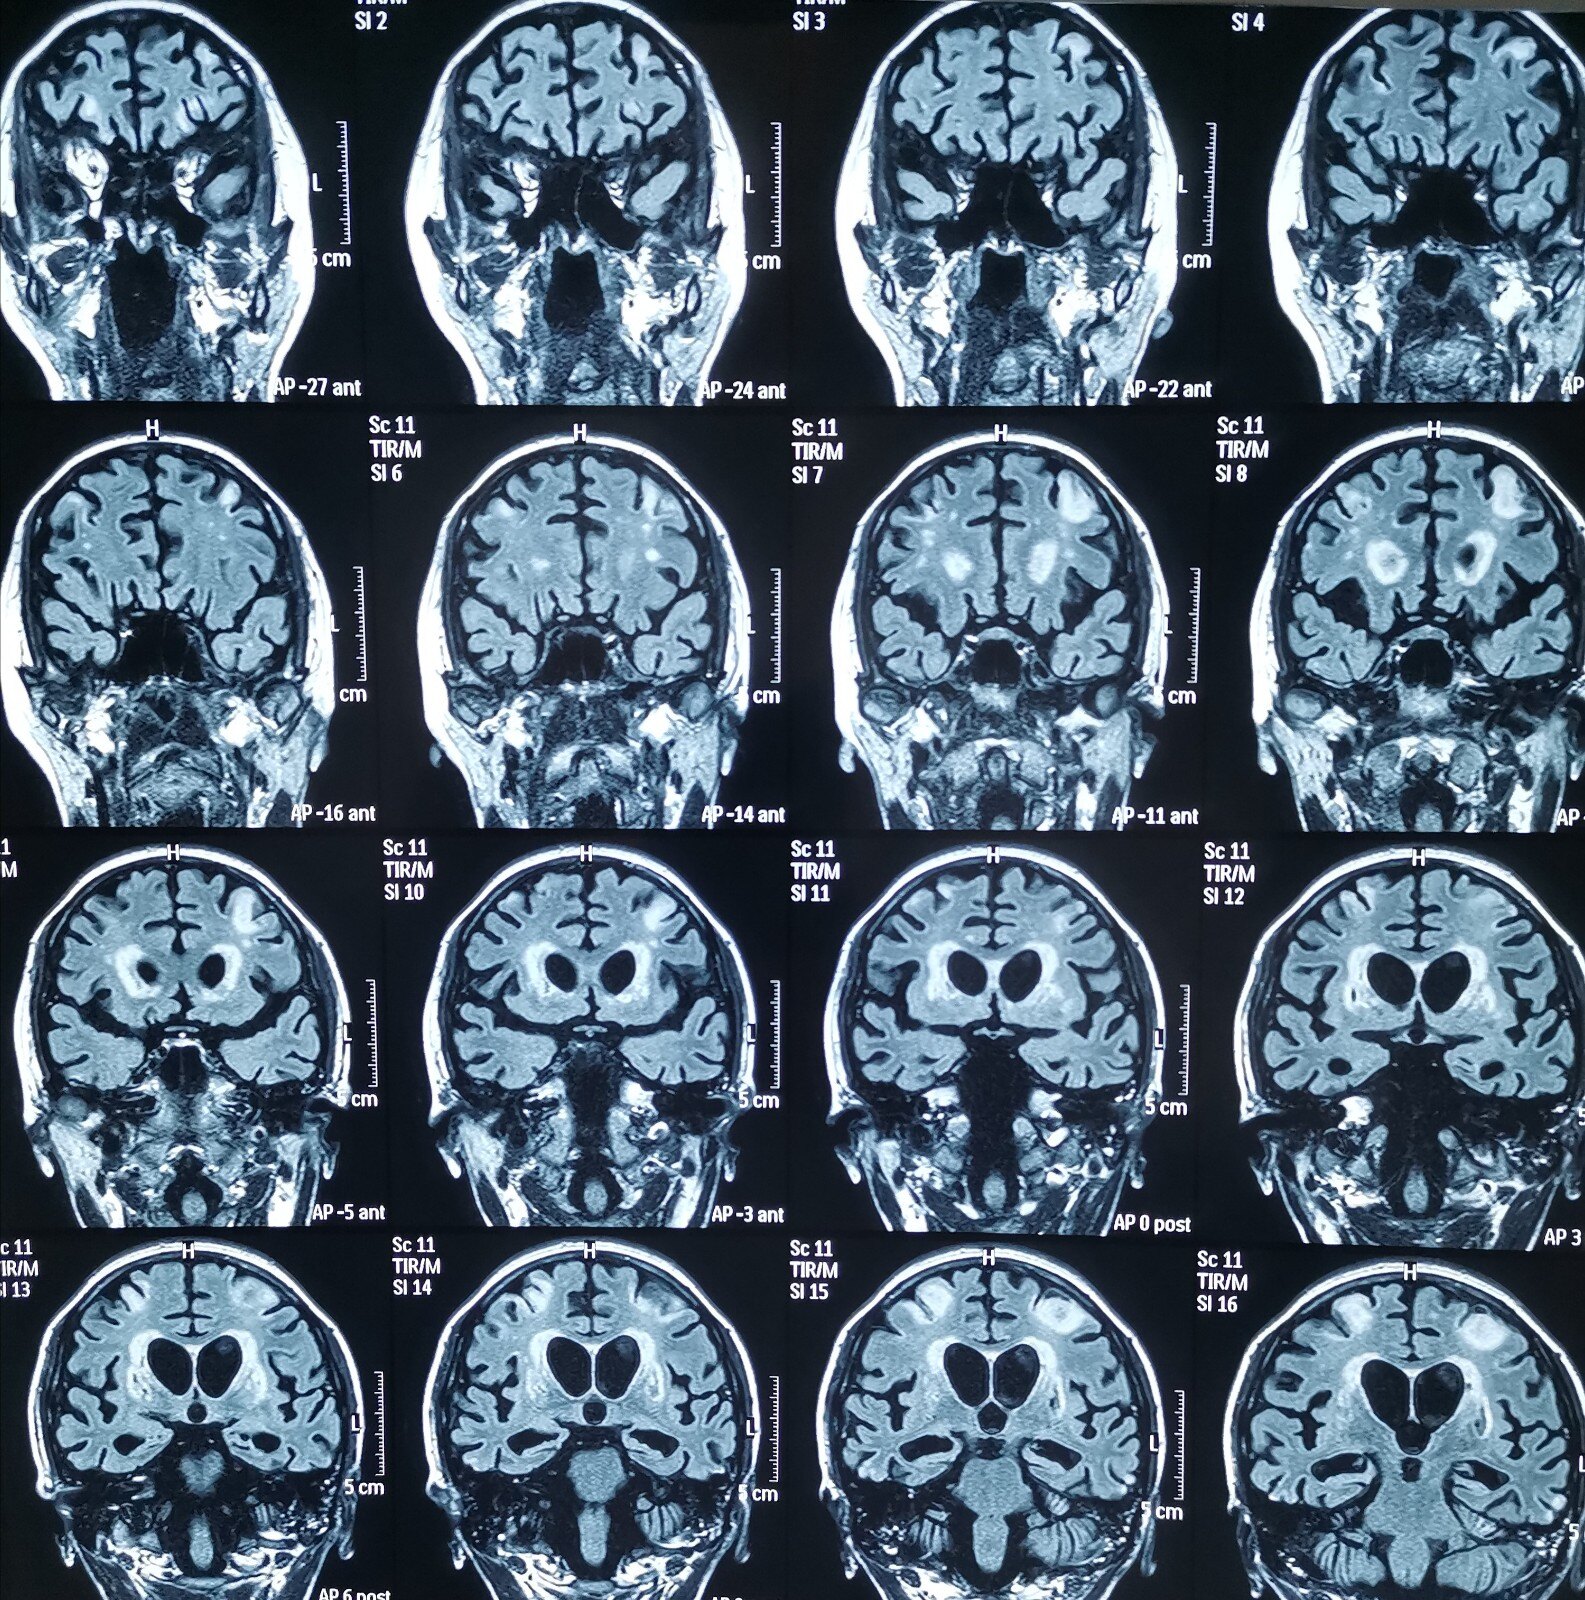

头部核磁平扫可见左侧大脑半球多发梗死灶,这就是患者反复缺血发作

阅片是有双侧大脑缺血灶,仔细看双侧小脑半球脑沟增多

两侧半卵圆中心,右侧基底节区多发缺血腔梗灶